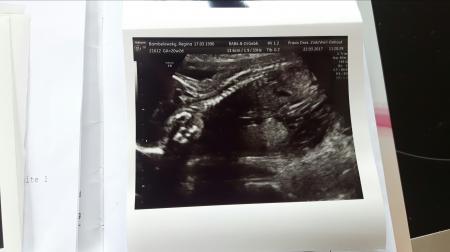

Huhu meine Lieben. Waren heute beim grossen Ultraschall. Bein unserem Spatzl ist alles in bester Ordnung 260 Gramm leicht und die SSL konnte nicht ermittelt werden, da es in Häschenstellung auf der Plazenta lag. Es ist alles zeitgerecht entwickelt und sieht super aus. Es trinkt fleißig Fruchtwasser Blase war ordentlich gefühlt. Auch bei mir ist alles gut die Plazenta ist wunderschön meinte sie und auch beim Fruchtwasser seien keine Auffälligkeiten. Nun zum Outing. Wir verstärken zu über 70% Team Rosa *freu* somit hatte der chinesische Kalender Recht bei mir. Ich freu mich so das alles in Ordnung ist. Lg Regina

Ja sie ernähren sich ja dadurch. Die Ärztin war sehr zufrieden da es ein Zeichen guter Nierenfunktion ist und das sie trinken kann. Hab mein Foto noch vergessen .

Bild zu